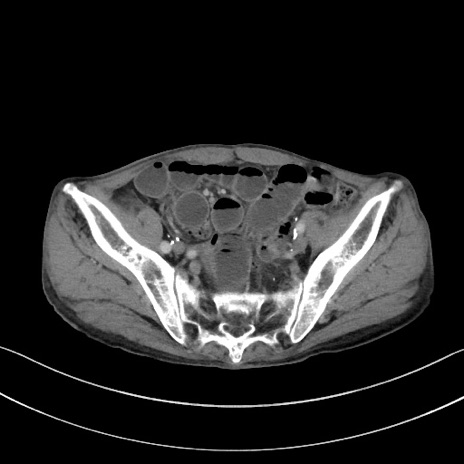

症例3(横断像)

【症例】 70歳代男性

【主訴】右鼠径部腫瘤、疼痛

【現病歴】本日朝より上記主訴あり、受診。

【既往歴】膀胱癌にて膀胱全摘、両側尿管皮膚瘻

【データ】WBC 5600、CRP 0.56